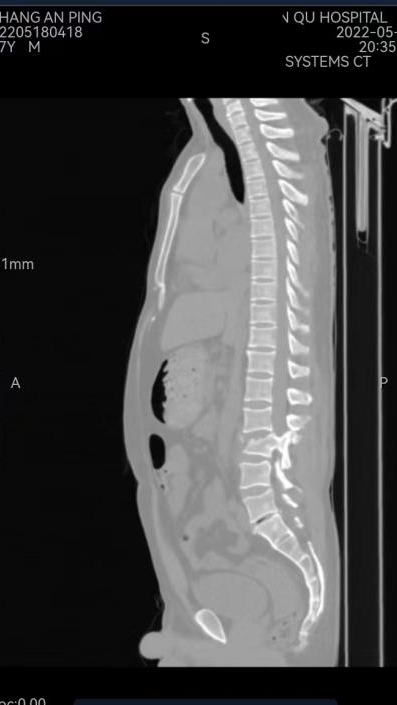

当患者到达急诊科抢救室时,创伤中心第一时间开通抢救绿色通道,为重伤患者进行快速救治。患者为一名57岁的男性患者,入院后,急诊外科值班医师快速了解情况,检查伤情。患者神志清,精神差,贫血貌,左侧胸廓塌陷,反常呼吸,左上腹肌紧张,压痛阳性,左下肢肌力1级,右下肢肌力0级。值班医生与值班护士陪同患者完善相关检查,初步诊断为:1、创伤性脾破裂伴创伤性休克代偿期2、腰3椎体chance骨折伴不全瘫3、多发肋骨骨折(左7-9前肋骨、左5-9腋肋、左侧5-12后肋)4、创伤性血气胸。

诊断明确后,医务部紧急召开会议,制定治疗方案:该名患者系车祸导致全身多发伤,复合伤,必须遵循”抢救生命第一“及”损伤控制“原则。目前创伤性湿肺严重并创伤性休克代偿期,应第一时间给气管插管及输血,保持肺通气,维持生命体征,在完善术前检查的同时积极行手术治疗;考虑患者脾破裂,应第一时间请普外科救治,终止危及生命的大出血;在病情稳定后,尽早请骨外科2组行骨科手术治疗,解除神经压迫,最大限度为术后下肢功能恢复创造条件;最后应请胸外科行手术治疗,治疗肋骨骨折及血气胸。同时麻醉手术部、检验科、影像中心及中心血库应全力支持,为此次多学科救治团队保驾护航,ICU应时刻准备,患者术后应送往ICU进一步复苏及治疗。

术后患者生命体征平稳,转ICU进一步支持治疗后再次送入手术室,麻醉科卢斌主任带领麻醉团队实施全麻后,骨外科2组曹炯哲团队给予行腰3椎体Chance骨折切开复位,椎板切开减压,腰2-3椎体植骨融合,椎弓根钉内固定术。随后胸外科左军涛主任带领团队给予行胸廓成型+肋骨骨折切开复位内固定+胸腔闭式引流术。手术总历时8小时。术后患者转ICU进一步生命监测及支持对症治疗。